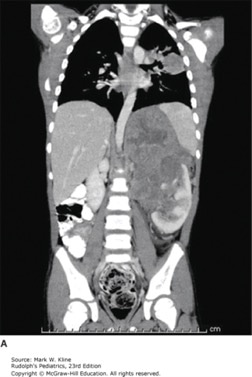

Coronal (A) and axial (B) images of child presenting with stage IV favorable histology Wilms tumor. Images demonstrate large left renal mass and massive pulmonary nodules.

Source: Kline MW. Rudolph's Pediatrics, 23rd ed. New York, NY: McGraw-Hill Education; 2018.